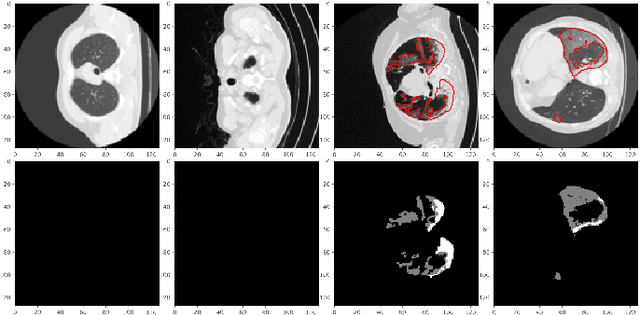

Abstract:The novel corona-virus disease (COVID-19) pandemic has caused a major outbreak in more than 200 countries around the world, leading to a severe impact on the health and life of many people globally. As of mid-July 2020, more than 12 million people were infected, and more than 570,000 death were reported. Computed Tomography (CT) images can be used as an alternative to the time-consuming RT-PCR test, to detect COVID-19. In this work we propose a segmentation framework to detect chest regions in CT images, which are infected by COVID-19. We use an architecture similar to U-Net model, and train it to detect ground glass regions, on pixel level. As the infected regions tend to form a connected component (rather than randomly distributed pixels), we add a suitable regularization term to the loss function, to promote connectivity of the segmentation map for COVID-19 pixels. 2D-anisotropic total-variation is used for this purpose, and therefore the proposed model is called "TV-UNet". Through experimental results on a relatively large-scale CT segmentation dataset of around 900 images, we show that adding this new regularization term leads to 2\% gain on overall segmentation performance compared to the U-Net model. Our experimental analysis, ranging from visual evaluation of the predicted segmentation results to quantitative assessment of segmentation performance (precision, recall, Dice score, and mIoU) demonstrated great ability to identify COVID-19 associated regions of the lungs, achieving a mIoU rate of over 99\%, and a Dice score of around 86\%.